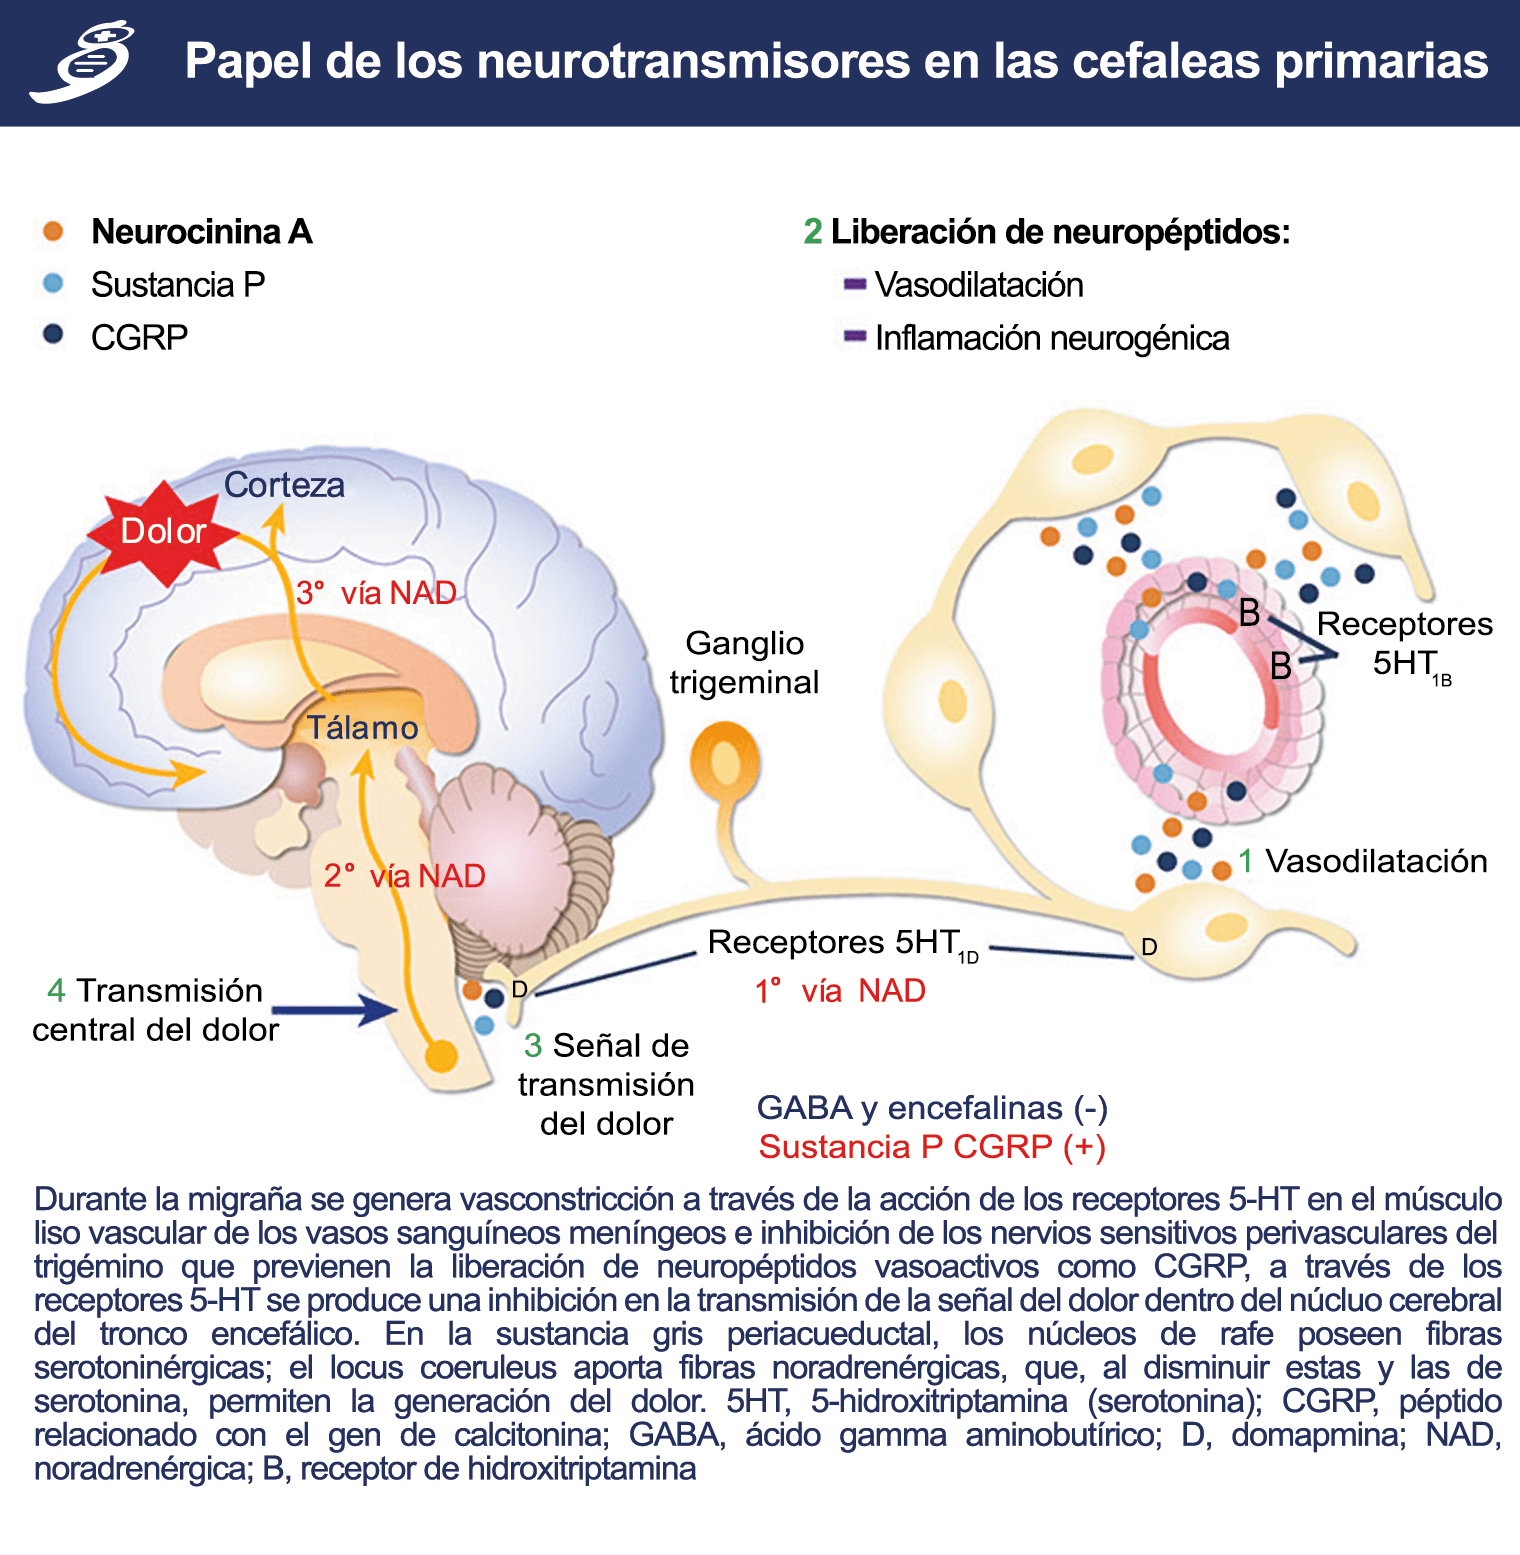

La comprensión de la biología de la migraña a través de una cuidadosa investigación de laboratorio ha llevado al desarrollo de las principales clases de tratamientos: triptanos, agonistas del receptor de serotonina 5-HT1B/1D; gepants, antagonistas del receptor del péptido relacionado con el gen de la calcitonina (CGRP); ditanes, agonistas del receptor 5-HT1F, CGRP anticuerpos monoclonales; moduladores de mGlu5, sin olvidar el efecto ya demostrado por parte de los bloqueantes de los canales de calcio (flunarizina) y de los neuromoduladores; bien se trate de topiramato (Inhibe la acción de la anhidrasa carbónica, bloquea los canales del sodio, aumenta las corrientes de cloro mediadas por GABA, activa las corrientes hiperpolarizantes del K+ e inhibe la activación de receptores a ácido glutámico tipo AMPA), valproato de sodio (Inhibe las enzimas de degradación del GABA y puede aumentar su síntesis, además de tener un papel inhibidor de la transmisión excitatoria de ciertos aminoácidos, entre ellos el glutámico y reducir el umbral de conductancia del calcio y el potasio) y de los antidepresivos de diversas clases como la amitriptilina (antidepresivo tricíclico que impide la recaptación y la inactivación de la noradrenalina y la serotonina en las terminaciones nerviosas) y venlafaxina (inhibe principalmente la recaptación de serotonina y en menor grado de noradrenalina, en la membrana presináptica neuronal, potenciando la neurotransmisión a nivel del sistema nervioso central). El propanolol tiene un efecto antagonista de los adrenoceptores β1 en las neuronas del núcleo VPM (postero medial ventral) del tálamo que responden a la entrada nociceptiva trigeminovascular. Se ha demostrado que el propanolol previene los cambios en el comportamiento y el flujo sanguíneo cerebral inducido por la depresión cortical propagada, además de bloquear los canales de sodio del cerebro(103), modulación del sistema catecolaminérgico central(104) probablemente a través de receptores β-adrenérgicos centrales e interacción cruzada con receptores de serotonina(105) (Figura 4).

Siendo el tálamo el centro principal para el procesamiento de la información nociceptiva sensorial en el cerebro, la transmisión de esta información para su procesamiento en las estructuras corticales donde los individuos la perciben es un factor clave. (Figura 18) Los tratamientos agudos como los “triptanos” (agonistas de los receptores 5-HT1B/1D)(29) y los antagonistas de los receptores CGRP(30) pueden inhibir las entradas nociceptivas durales agudas. Del mismo modo, los preventivos de la migraña propranolol(31), valproato de sodio(32) y topiramato(33)también pueden inhibir las entradas trigeminotalámicas nociceptivas durales en el VPM (Núcleo ventral posteromedial).

La activación del sistema trigeminovascular da como resultado la liberación de varios neuropéptidos basados en las inervaciones simpática, parasimpática y sensorial de la vasculatura craneal, que se resumen en la figura 23.

La inervación simpática se caracteriza por NPY y norepinefrina(52), ambos de los cuales son vasoconstrictores, mientras que las fibras parasimpáticas se caracterizan por VIP y PACAP, que se encuentran entre los vasodilatadores más potentes(24).

Las inervaciones sensoriales se caracterizan por la sustancia P, CGRP y PACAP (53).

La serotonina

La participación inicial de la serotonina (5-HT) en la migraña fue postulada hace más de 50 años.(54) (Figura 24)

Posteriormente diversos estudios demostraron que la infusión de 5-HT podría abortar tanto la cefalea inducida por reserpina(55) como la espontánea(56). En respuesta a estos estudios, el sistema del receptor 5-HT ganó mucha atención, lo que culminó con el descubrimiento de los triptanos, la serotonina y los agonistas del receptor 5-HT1B/1D(57). Todos exceptuando el 5-HT3 (canal iónico controlado por ligando) son receptores acoplados a proteína G. Si bien los triptanos se clasifican como agonistas de los receptores 5-HT1B/1D, la mayoría también activa en menor medida los receptores 5-HT1A, 5-HT1E o 5-HT1F(58). Originalmente, los triptanos se desarrollaron para actuar sobre la vasculatura craneal, una idea apoyada por sus claras acciones vasoconstrictoras(59) (Figura 25) y la expresión preferencial del receptor 5-HT1B en los vasos craneales más que en los periféricos(60).

Un mecanismo neural de los triptanos en las terminaciones del nervio trigémino periférico podría inhibir la liberación de neuropéptidos proinflamatorios y la vasodilatación dural neurogénica(63), lo cual era consistente con el tema en desarrollo de la migraña como una enfermedad neurovascular. (Figuras 26 y 27)

Teniendo en cuenta uno de los efectos iniciadores de la migraña, como la depresión cortical propagada, que probablemente es causada por una alteración de la permeabilidad neuronal y tiene una disfunción posterior de canales iónicos, es importante recalcar la presencia de dos mecanismos neuronales subyacentes: la sensibilización periférica y la sensibilización central(85). Las estructuras sensitivas intracraneanas reciben inervación de ramas del trigémino estimuladas por liberación neuronal y endotelial, abriendo receptores en las terminales neurogénicas. Esto lleva al incremento de la concentración de calcio intracelular, seguido de fosforilación y activación de proteincinasa (PKC) y tirosincinasa (TryK) que, a su vez, por mecanismos moleculares aumenta la liberación de sustancias como la CGRP y VIP y promueve la inflamación neurogénica. Este proceso conduce a la sensibilización periférica dada por la disminución del umbral de respuesta de las fibras meníngeas, potenciándose el dolor y la inflamación(86). Por otra parte Las concentraciones de serotonina, la cual se forma a partir del L-triptófano, son altas en las plaquetas y en el tracto gastrointestinal. Este hecho adquiere crucial importancia ya que la serotonina viaja por el torrente sanguíneo hasta el cerebro donde sufre procesos de hidroxilación y descarboxilación para realizar sus funciones a nivel central(22). Las neuronas ricas en esta sustancia se encuentran alrededor del tallo cerebral y de la formación reticular en especial en el núcleo caudalis del trigémino en donde no solo donde tienen la mayor concentración de serotonina, también estas neuronas predominantemente serotoninérgicas se encuentran en mayor concentración, lo cual es un factor especial para desencadenar el proceso de activación del sistema trigémino vascular en el ataque de migraña. Los receptores especiales de 5HT, al activarse, incrementan la hidrólisis de inositol fosfato y generan un aumento de la concentración de calcio en el proceso migrañoso. Además de la serotonina existen diferentes sustancias involucradas en el desarrollo de la cefalea como los receptores dopaminérgicos y la histamina, que tienen efectos vasculares de vasoconstricción o vasodilatación. Existe una hipersensibilidad dopaminérgica en la migraña y en lo que respecta a la histamina, se ha visto incrementada a nivel plasmático por una posible liberación a partir de los leucocitos o por la activación de células mastocitarias. Aunque la histamina no cruza la barrera hematoencefálica esta actúa a través de receptores H1 que están en el endotelio(88).